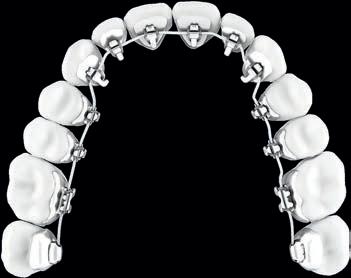

l Moderne & unsichtbare Zahnspangen

l Für Kinder, Jugendliche und Erwachsene

l Alle Kassen

Dr. med. dent. Dorothea Endler Fachzahnärztin für Kieferorthopädie

Hohenzollernring 59 48145 Münster

Tel. 02 51-14 98 48 90